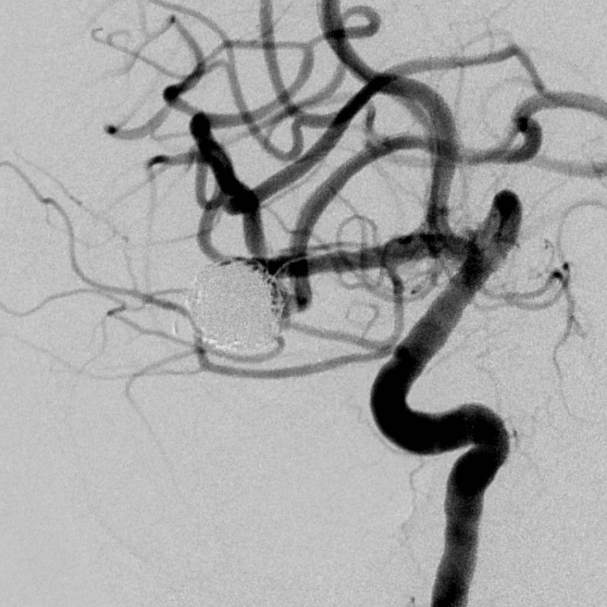

粗大分支从破裂瘤体上发出来,急性期能单纯致密栓塞吗?

病史:中年女性,新冠感染,颅内动脉瘤破裂,Hunt-Hess 4级

最终,动脉瘤瘤体致密栓塞,各个分支保留良好